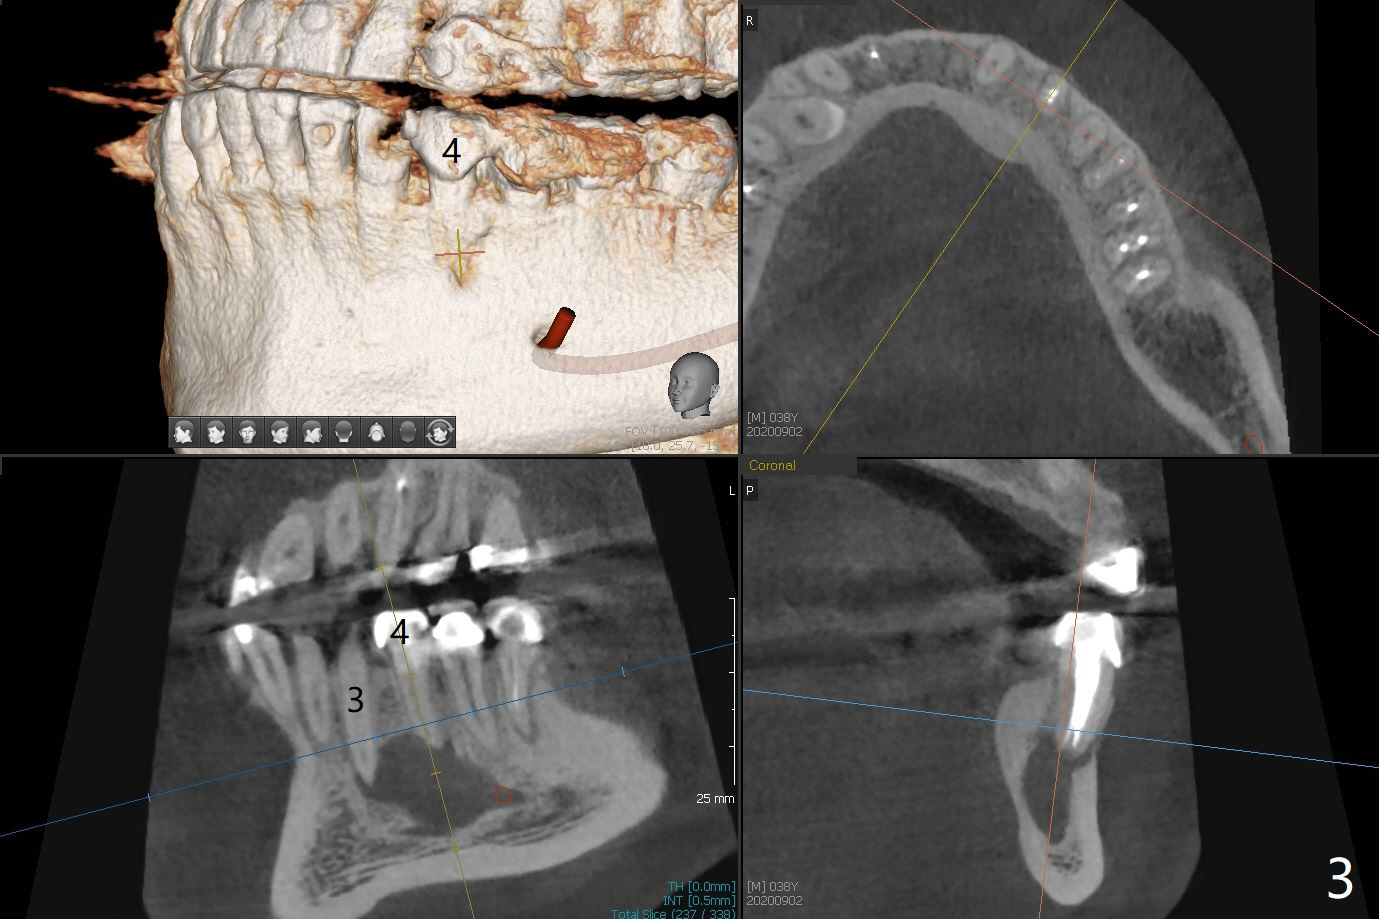

38岁男,十几岁左下4在台湾做根管治疗,八年前外州美国牙医重做根管治疗,他成为我们病人约五年,根尖阴影一直存在,由于无症状,没有引起重视。不过近半年主诉左下唇偶尔麻木,全景片似乎显示左下4根尖阴影相当大,今天CT检查证实这一点(图一),仿佛是根尖囊肿;右下前磨牙区多生牙(*),右上8颊侧也有一个多生牙(图二:8')。虽然病人恐惧手术,但是他不愿意去看专家。尽管囊肿大,累及邻牙,尤其是左下三(图三(可能死髓,Endo Ice; Electric Pulpal Tester;根管治疗)),但是首先做根尖半月形切口,做比较大的根尖切除术,试图刮治囊肿。如果手术当时刮治不全,拔除患牙,增加视野,彻底刮治,填入大量粘性骨块(图四:红圆圈),覆盖PRF膜,缝合,牙周敷料。由于工作需要,病人说他不能没有牙,如果可能,做即刻植牙(图四:绿色),即刻无咬合修复。准备Collagen or Osteogen Plugs,压迫止血。